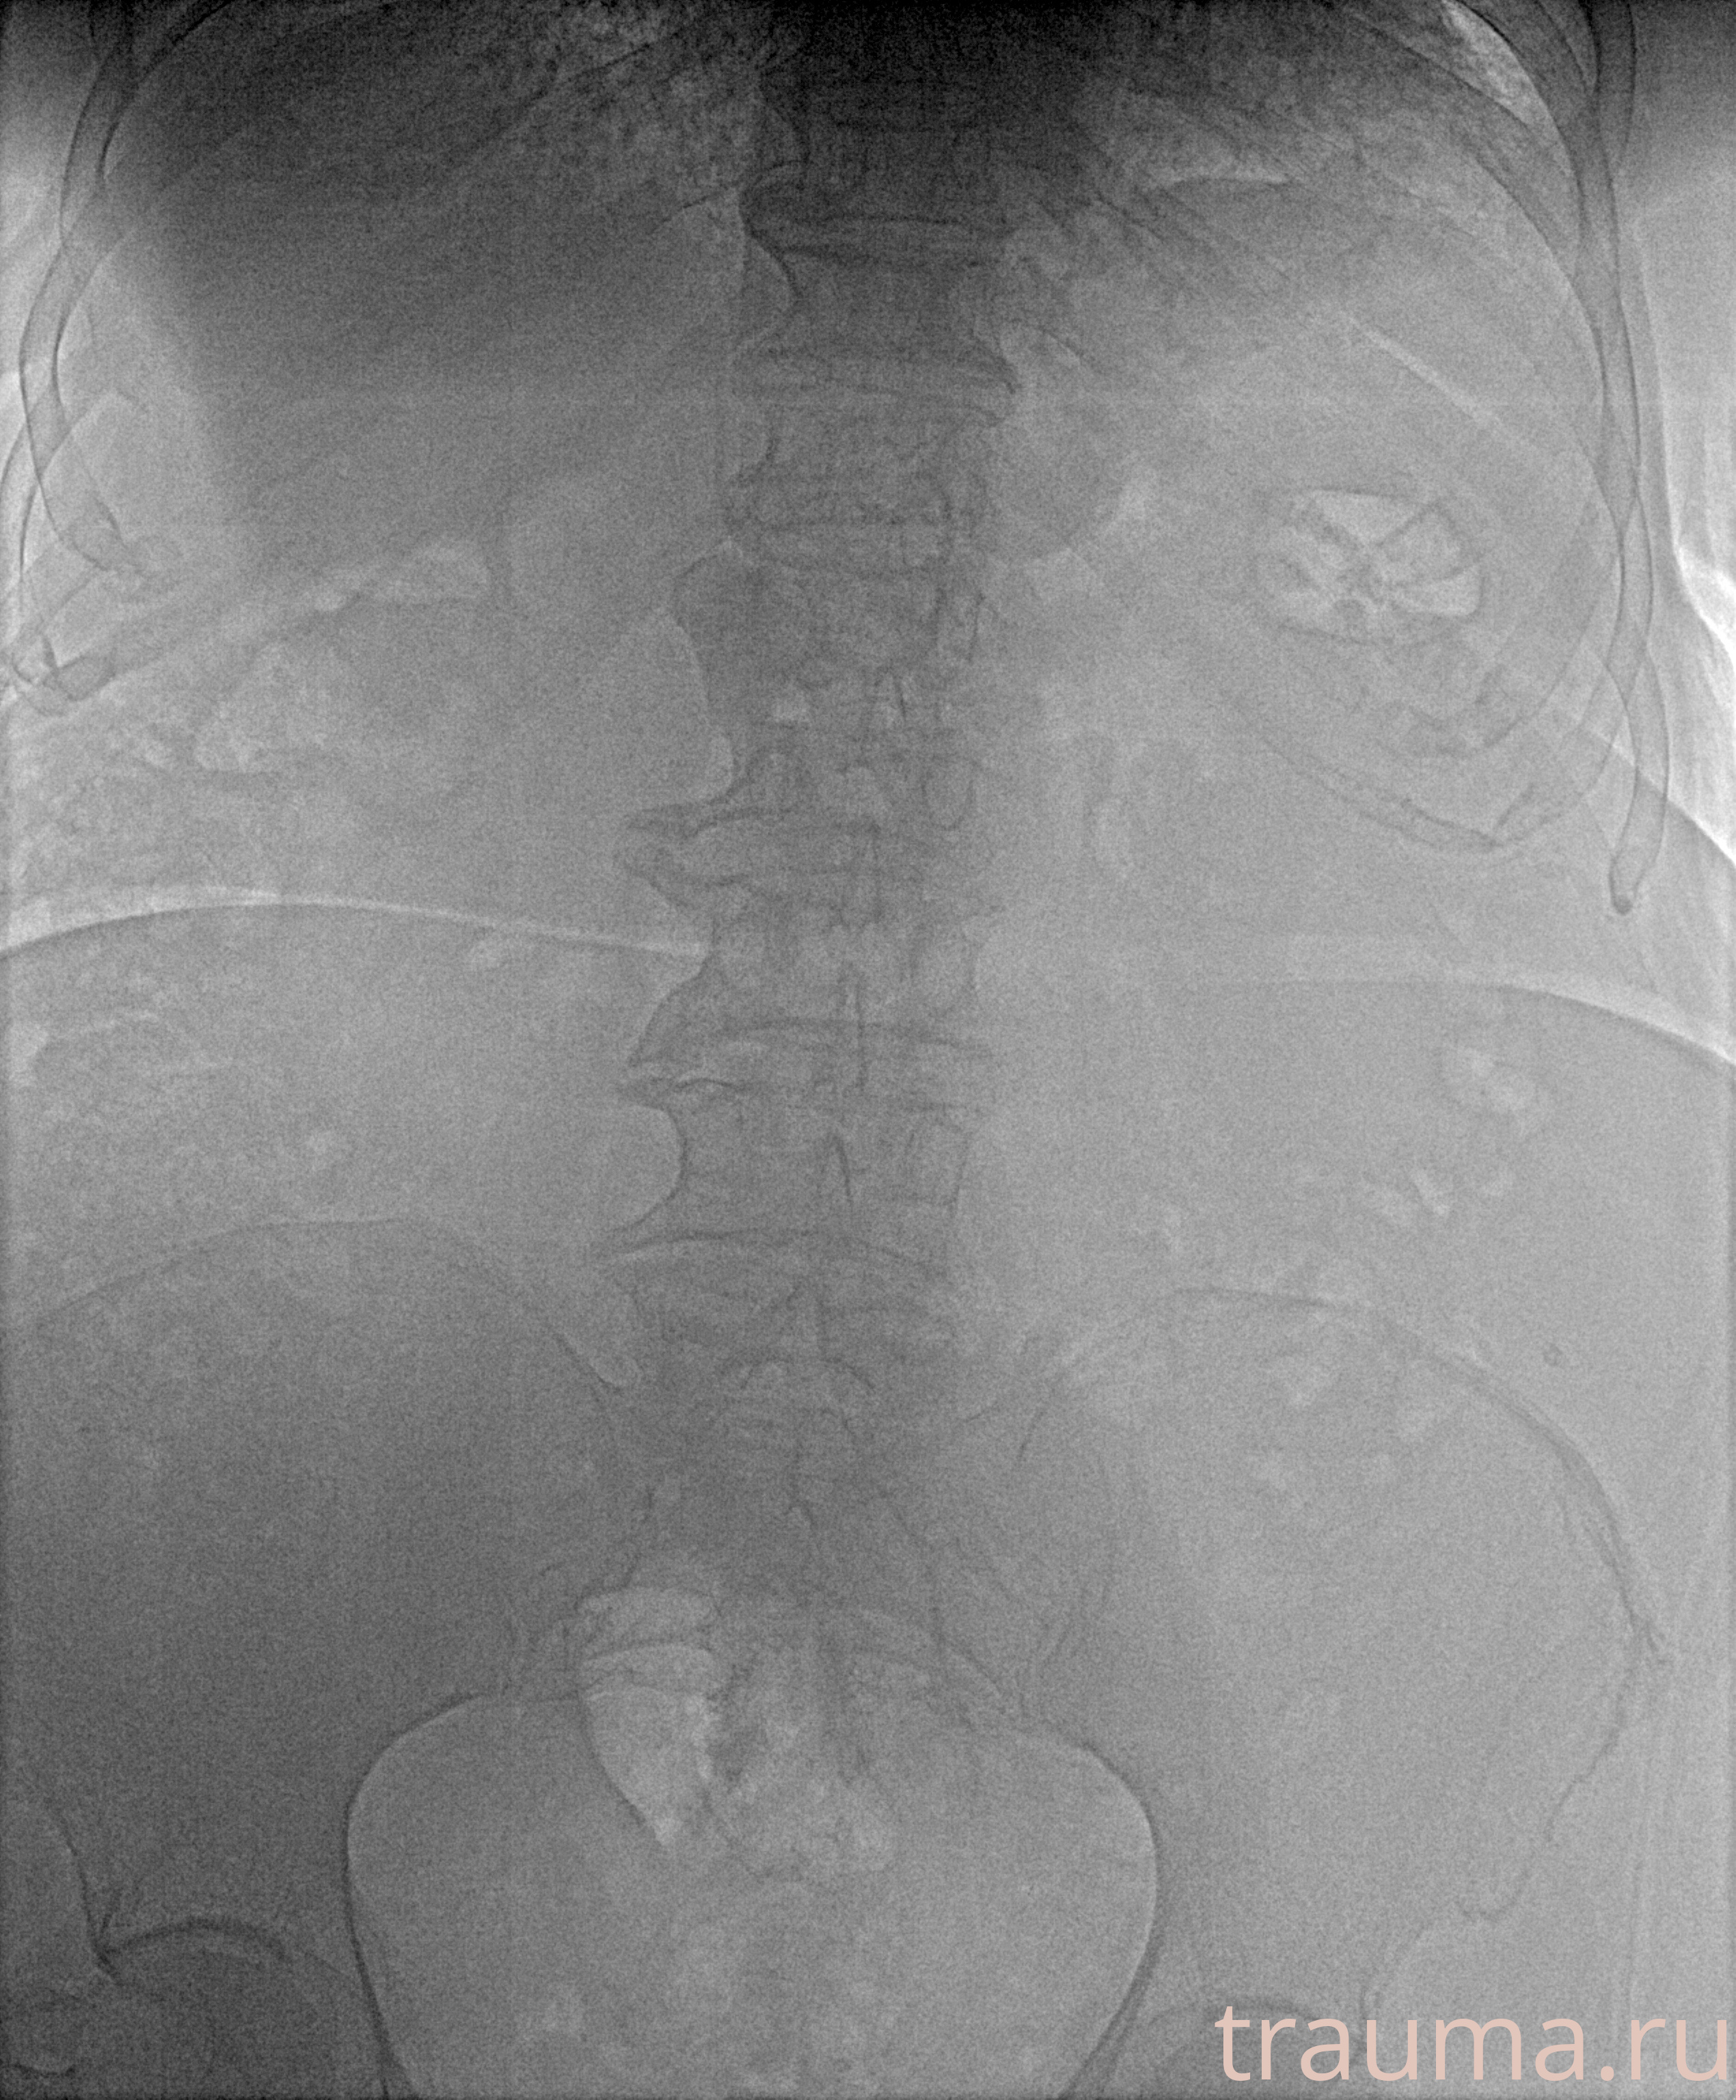

Рентген на дому: по вашему адресу приезжает врач-рентгенолог, травматолог-ортопед с мобильным рентгеновским аппаратом, проводит диагностику травмы или заболевания, делает необходимые рентгенограммы, дает рекомендации по дальнейшему лечению. Получить качественные снимки в домашних условиях возможно благодаря уникальной методике, разработанной МосРентген Центром для института  Склифосовского

при переломе шейки бедра и пневмонии от компании МосРентген Центр - партнера Института имени Склифосовского